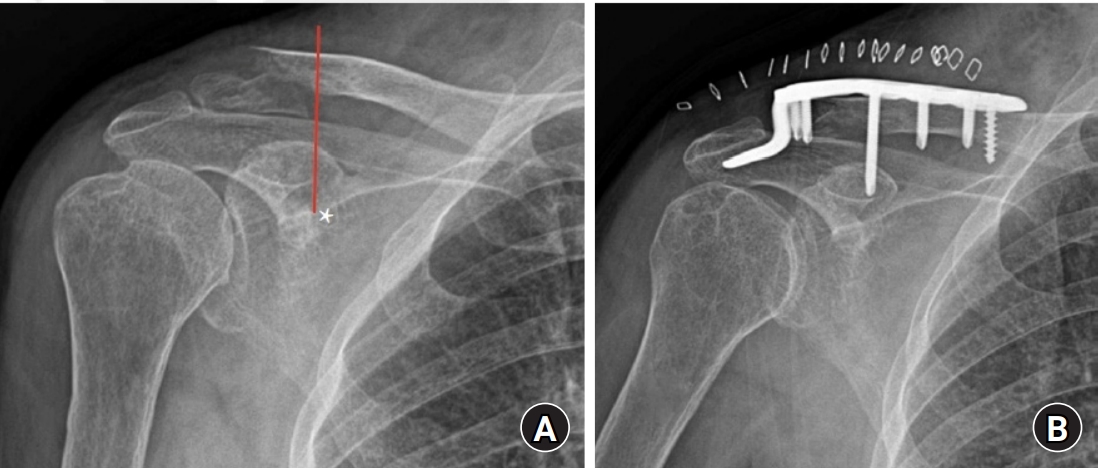

Fig. 5.

On a caudal view of the clavicle, the conoid tubercle (asterisk) of the lower surface of the clavicle was in accordance with the possibility of three-screw fixation in all models (A, B). In the comminuted clavicular fracture, which was fixed with a pelvic curved recon plate through the bridge plating technique, a postoperative biplanar 3-dimentional image shows that the lateral fragment lateral to the conoid tubercle (asterisk) could be fixed with three screws (C, D).

3D Analysis of Virtually Fixed Shoulder

Compared with the virtually placed plate in the ideal position, on the cranial view, the elevated ridge of 51 models was centrically matched with a central point of plate hole (third hole in 48 models, second hole in two models, and fourth hole in one model) and 39 models, eccentrically with the third hole (Table 1). On an AP view of the shoulder, the intersection point between the imaginary vertical line from the medial border of coracoid process and distal clavicle was always placed in the medial to the third hole of plate regardless of the degree of horizontal rotation of scapula (Fig. 4). On the lower surface of clavicle, the conoid tubercle was in accord with the possibility of three screws fixation in all models (Fig. 5). The findings clearly demonstrated that the distal clavicular fragment, which corresponded to the medial border of coracoid process and conoid process, had fixability of at least three screws through the plate.